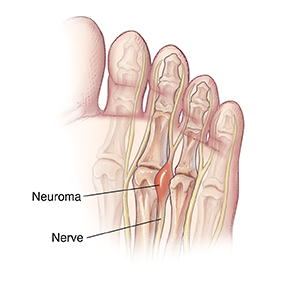

Neuroma

When 2 metatarsal bones are squeezed together, they may pinch the nerve that runs between them. The pinched nerve can become swollen and painful. This often happens at the base of the third and the fourth toes. Standing or walking for a while can increase the pain.